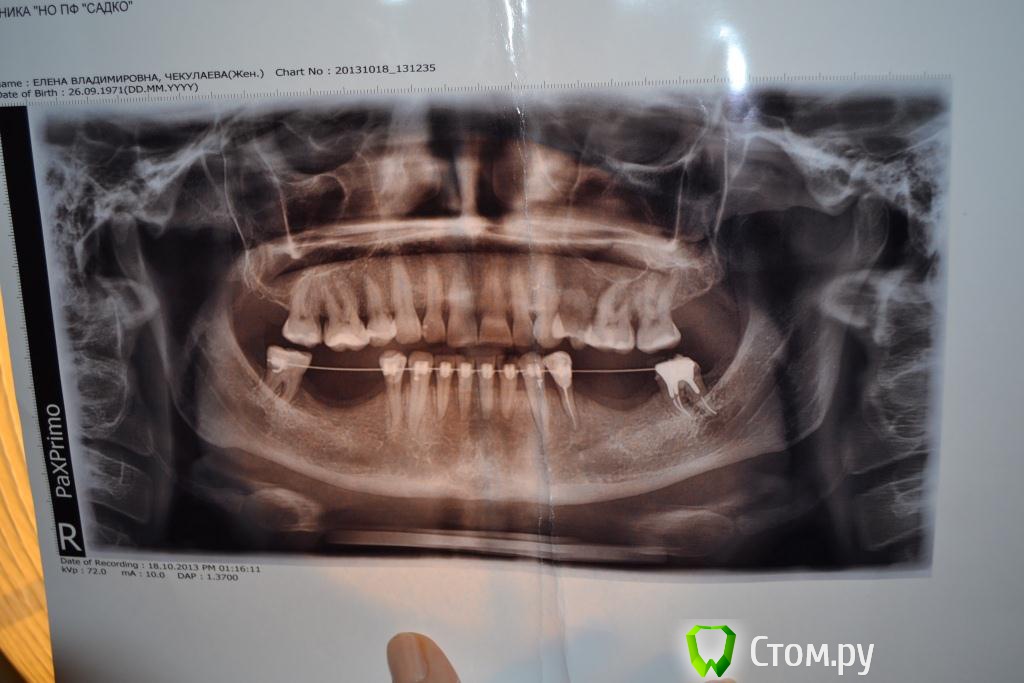

luda77 Опубликовано 19 ноября, 2013 Автор Поделиться Опубликовано 19 ноября, 2013 (изменено) Спасибо за добрые слова. Я немного успокаиваюсь. Вот мои снимки: панорамный до, панорамный месяц назад, фото прикуса и попробую КТ присоединить (весь вечер пыхтела, надеюсь получится) ... Не получилось. Архивировала подпапку, где много файлов. Получилось 21 архивный файл по 1 400-это слишком много. Завтра у умных мужчин на работе спрошу-как. Изменено 19 ноября, 2013 пользователем luda77 Ссылка на комментарий

Ayrat_zub Опубликовано 19 ноября, 2013 Поделиться Опубликовано 19 ноября, 2013 Спасибо за добрые слова. Я немного успокаиваюсь. Вот мои снимки: панорамный до, панорамный месяц назад, фото прикуса и попробую КТ присоединить (весь вечер пыхтела, надеюсь получится) ... Не получилось. Архивировала подпапку, где много файлов. Получилось 21 архивный файл по 1 400-это слишком много. Завтра у умных мужчин на работе спрошу-как.так, а ТРГ вам, я так понимаю, не делали? Ссылка на комментарий

Ayrat_zub Опубликовано 19 ноября, 2013 Поделиться Опубликовано 19 ноября, 2013 (изменено) Спасибо за добрые слова. Я немного успокаиваюсь. Вот мои снимки: панорамный до, панорамный месяц назад, фото прикуса и попробую КТ присоединить (весь вечер пыхтела, надеюсь получится) ... Не получилось. Архивировала подпапку, где много файлов. Получилось 21 архивный файл по 1 400-это слишком много. Завтра у умных мужчин на работе спрошу-как.у вас стекрты резцы и клыки. с верхним зубным рядом, ортодонтиченская работа планировалсь? Изменено 19 ноября, 2013 пользователем Ayrat_zub Ссылка на комментарий